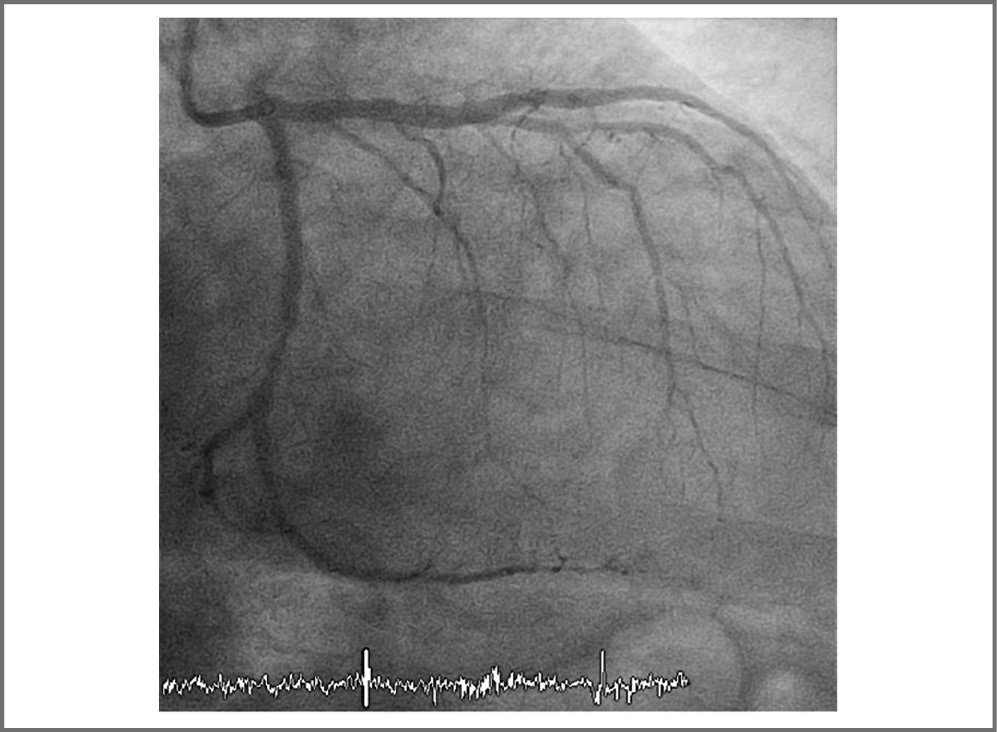

Пациент госпитализирован в региональный сосудис- тый центр. В связи с отсутствием признаков реперфузии на ЭКГ выполнена экстренная коронароангиография (КАГ), при которой выявлена окклюзия передней нисходящей артерии (ПНА) в проксимальном сегменте. Одномоментно выполнено ЧКВ со стентированием ПНА двумя стентами с лекарственным покрытием (рис. 1, 2). Процедура прошла без осложнений, кровоток по ПНА после вмешательства – TIMI III. По данным ЭКГ после вмешательства отмечаются признаки реперфузии в виде снижения элеваций сегмента ST.

Рис. 1. КАГ: до ЧКВ.

Рис. 2. КАГ: после ЧКВ.